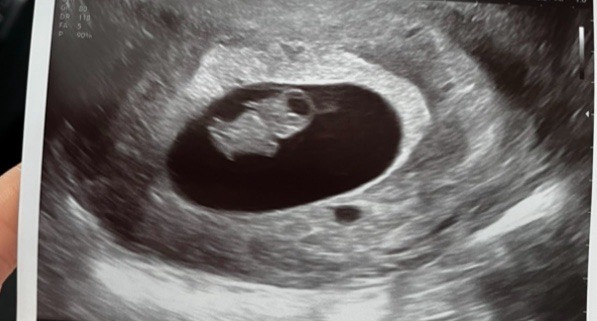

7주 6일차 젤리곰💙

우리애기 젤리곰 사진 보고왔는데 의사선생님도 볼살보고 빵터지셨네요ㅋㅋㅋㅋ 제 눈엔 저 오동통한 볼살마저 너무 귀여워요 몇번이나 초음파를 돌려봤는지.. 제 몸속에서 벌써 이만큼이나 자랐다는게 너무 신기해요